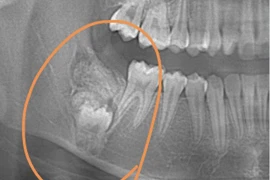

(khoahocdoisong.vn) - 80% nguyên nhân mất răng ở người từ 35 tuổi trở lên là do viêm nha chu nhưng rất ít người biết thông tin về bệnh. Ai cũng có nguy cơ mất răng nếu bị nha chu mà khôn phát hiện sớm. TS.BS Trần Hùng Lâm, Giám đốc chuyên môn nha khoa Elite sẽ chia sẻ về bệnh này.